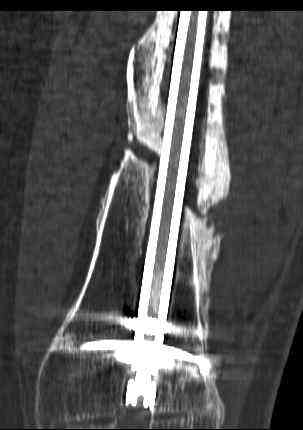

16 yr old boy, high energy motorcycle trauma trauma in July 2005 with:

- hip dislocation + acetabular fracture L

- distal femoral fracture L

- tibial shaft fracture L

- metatarsal fractures L

july 05: LISS femur, LCP plate tibia, double recon. plate post. acetabulum

oct 05: cancellous bone graft femur

aug 06: blade plate + bone graft

nov 06: revision blade plate

feb 07: retrograde nail + bone graft + BMP

may 07: dynamisation nail

sept 07: locking screw removal (max. dynamisation reached)

nov 07: persistant non-union distal femur; other fractures healed uneventfully.